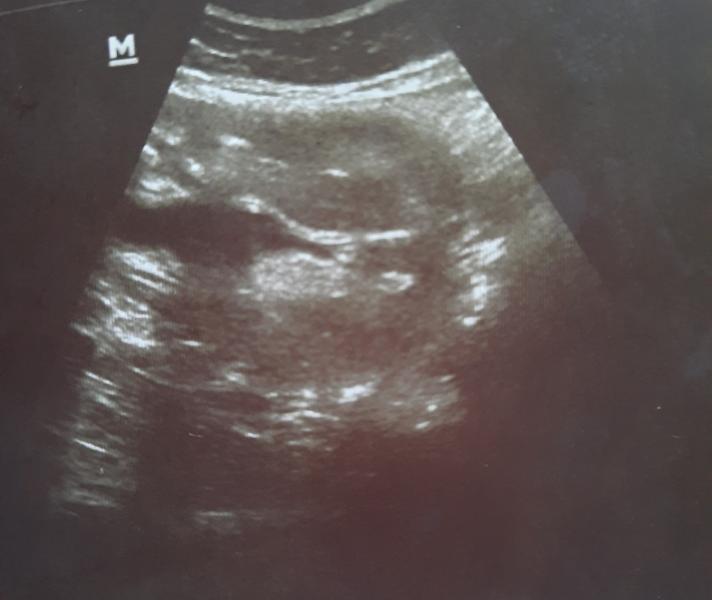

Ходила на узи и вновь путаница 🤣

Дали фото интимного места и сказали что может и мальчик,а может и девочка🤣

Дак вот,приглашаю вас девочки поразглядывать и поломать глазки ,пованговать😁

@kris_konovalova, а 3д не делали? Или лежит так, что плохо видно?

@anshtraukh делали,лежит плохо и вертится,вот это первое фото "удачное" так скажем🤣

@anshtraukh там нам и предположила на 70%мальчика,но сразу сказали это не точно

Мальчик